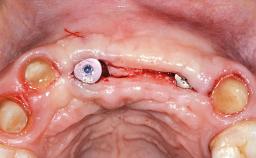

A 28-year-old female patient presented to our clinic in 2000 with failing teeth 11 and 21. She reported no general medical conditions that would prevent routine restorative and surgical procedures. She was experiencing no pain, but reported that the teeth were mobile and would like to replace them with something more permanent. Upon an extraoral and intraoral clinical examination and radiographic review, teeth 11 and 21 exhibited external and internal resorption, class II mobility, and periapical pathology. Given their poor prognosis for long-term survival, it was determined that they should be extracted. Several treatment options were considered, ranging from a conventional fixed dental prosthesis to single (cantilevered restoration) or multiple dental implants. Considering the patient’s desire to have individual teeth and the available architecture of the hard and soft tissue, it was determined that adjacent implantsupported restorations should be explored.